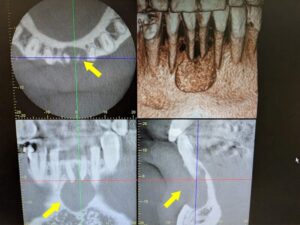

病院のスタッフにパノラマエックス線を撮りたいと言ってるのに、なぜかデンタルエックス線の準備をします。そうか私の英語が悪いのかあ、仕方ないこれは無理をしてもいけないので、デンタルエックス線で我慢しようと思いました。何回か同じことが繰り返され流石に何かおかしい?と思いスタッフに尋ねると..... 機械が壊れておりました。それでも病院スタッフは親知らずの抜歯希望の患者さんの予約を入れてくれてました。患者さんもやる気満々です。

レントゲンはありませんが、抜歯は無事に終わりました。理想的な環境とは言えないですが、結果としてゴールにはきちんと辿り着けました。

親知らずはレントゲンなしで、丁寧に抜歯いたしました。